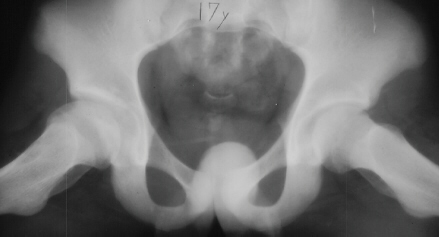

The parents first noted at the time the patient was 10y and 9 m old that he would limp on the right side after a full day of activity. He also started to have a occasional hip pain. Since the hip pain became progressively worse, he visited local clinics and was referred to AIDI at the age of 11y and 3 m. At the first examination abduction was 40 degrees bilaterally but internal rotation was limited to 0 degree on the right. The leg lengths were equal and no Trendelenburg sign was observed. X-ray showed the decreased epiphyseal height and medial joint opening. Snyder sling was started. At 12 years of age, internal rotation was still limited 20 degrees compared to 35 degrees on the left side but the left hip pain was asymptomatic. At 13 years of age, X-ray showed the regenerated head, so the Snyder sling was stopped and weight bearing was started. The Snyder sling had been applied for 2 years. At 16 years of age, ten degrees limitation of internal rotation as compared to the opposite side was still observed but the patient was asymptomatic.

11 yrs 3 mos, , 12 yrs, 13 yrs 8 mos , 17 yrs , 18 yrs.